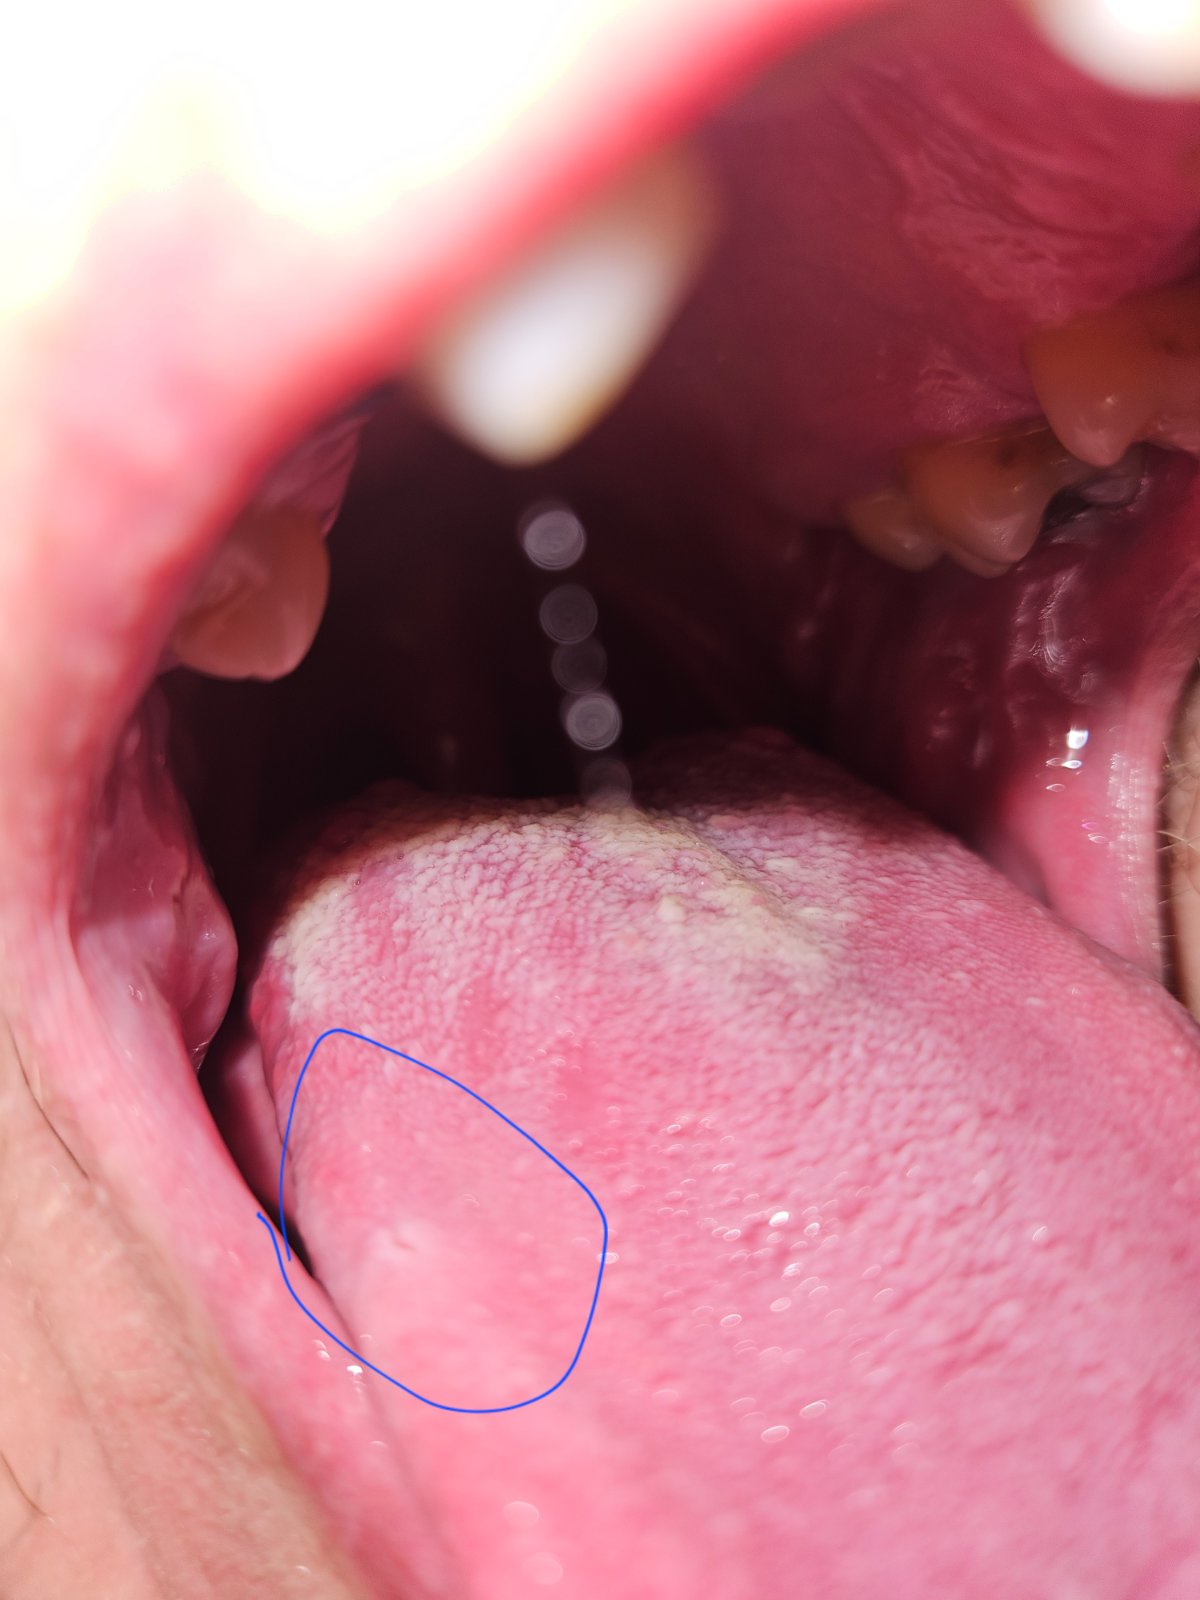

Mam takú bielu škvrnu na jazyku a je to bolestivé aj mate niekto prosím s niečím podobným skúsenosti???